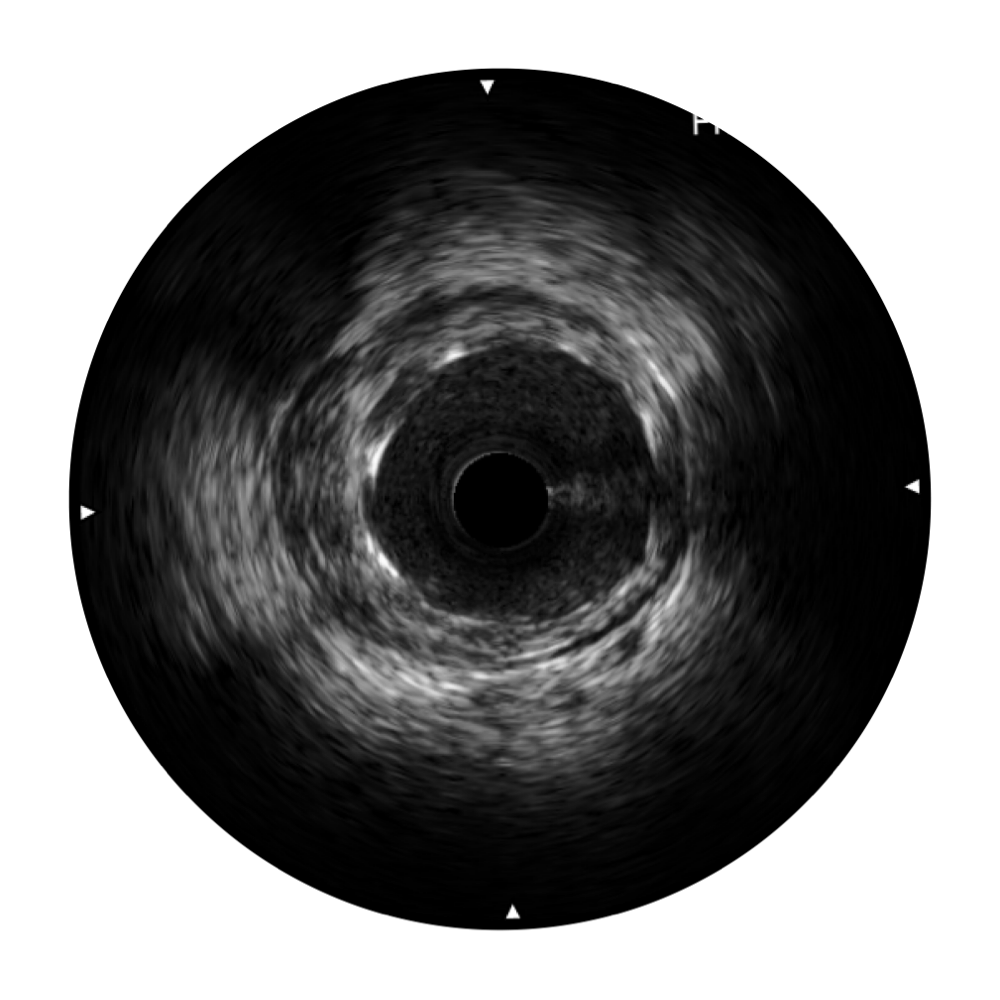

云顶集团官网宽频IVUS图像

对比传统IVUS导管成像,云顶集团官网宽频IVUS图像的近场支架梁显影更细腻,远场中膜外血管仍清晰可辨,兼顾远中近,兼顾分辨力与穿透深度